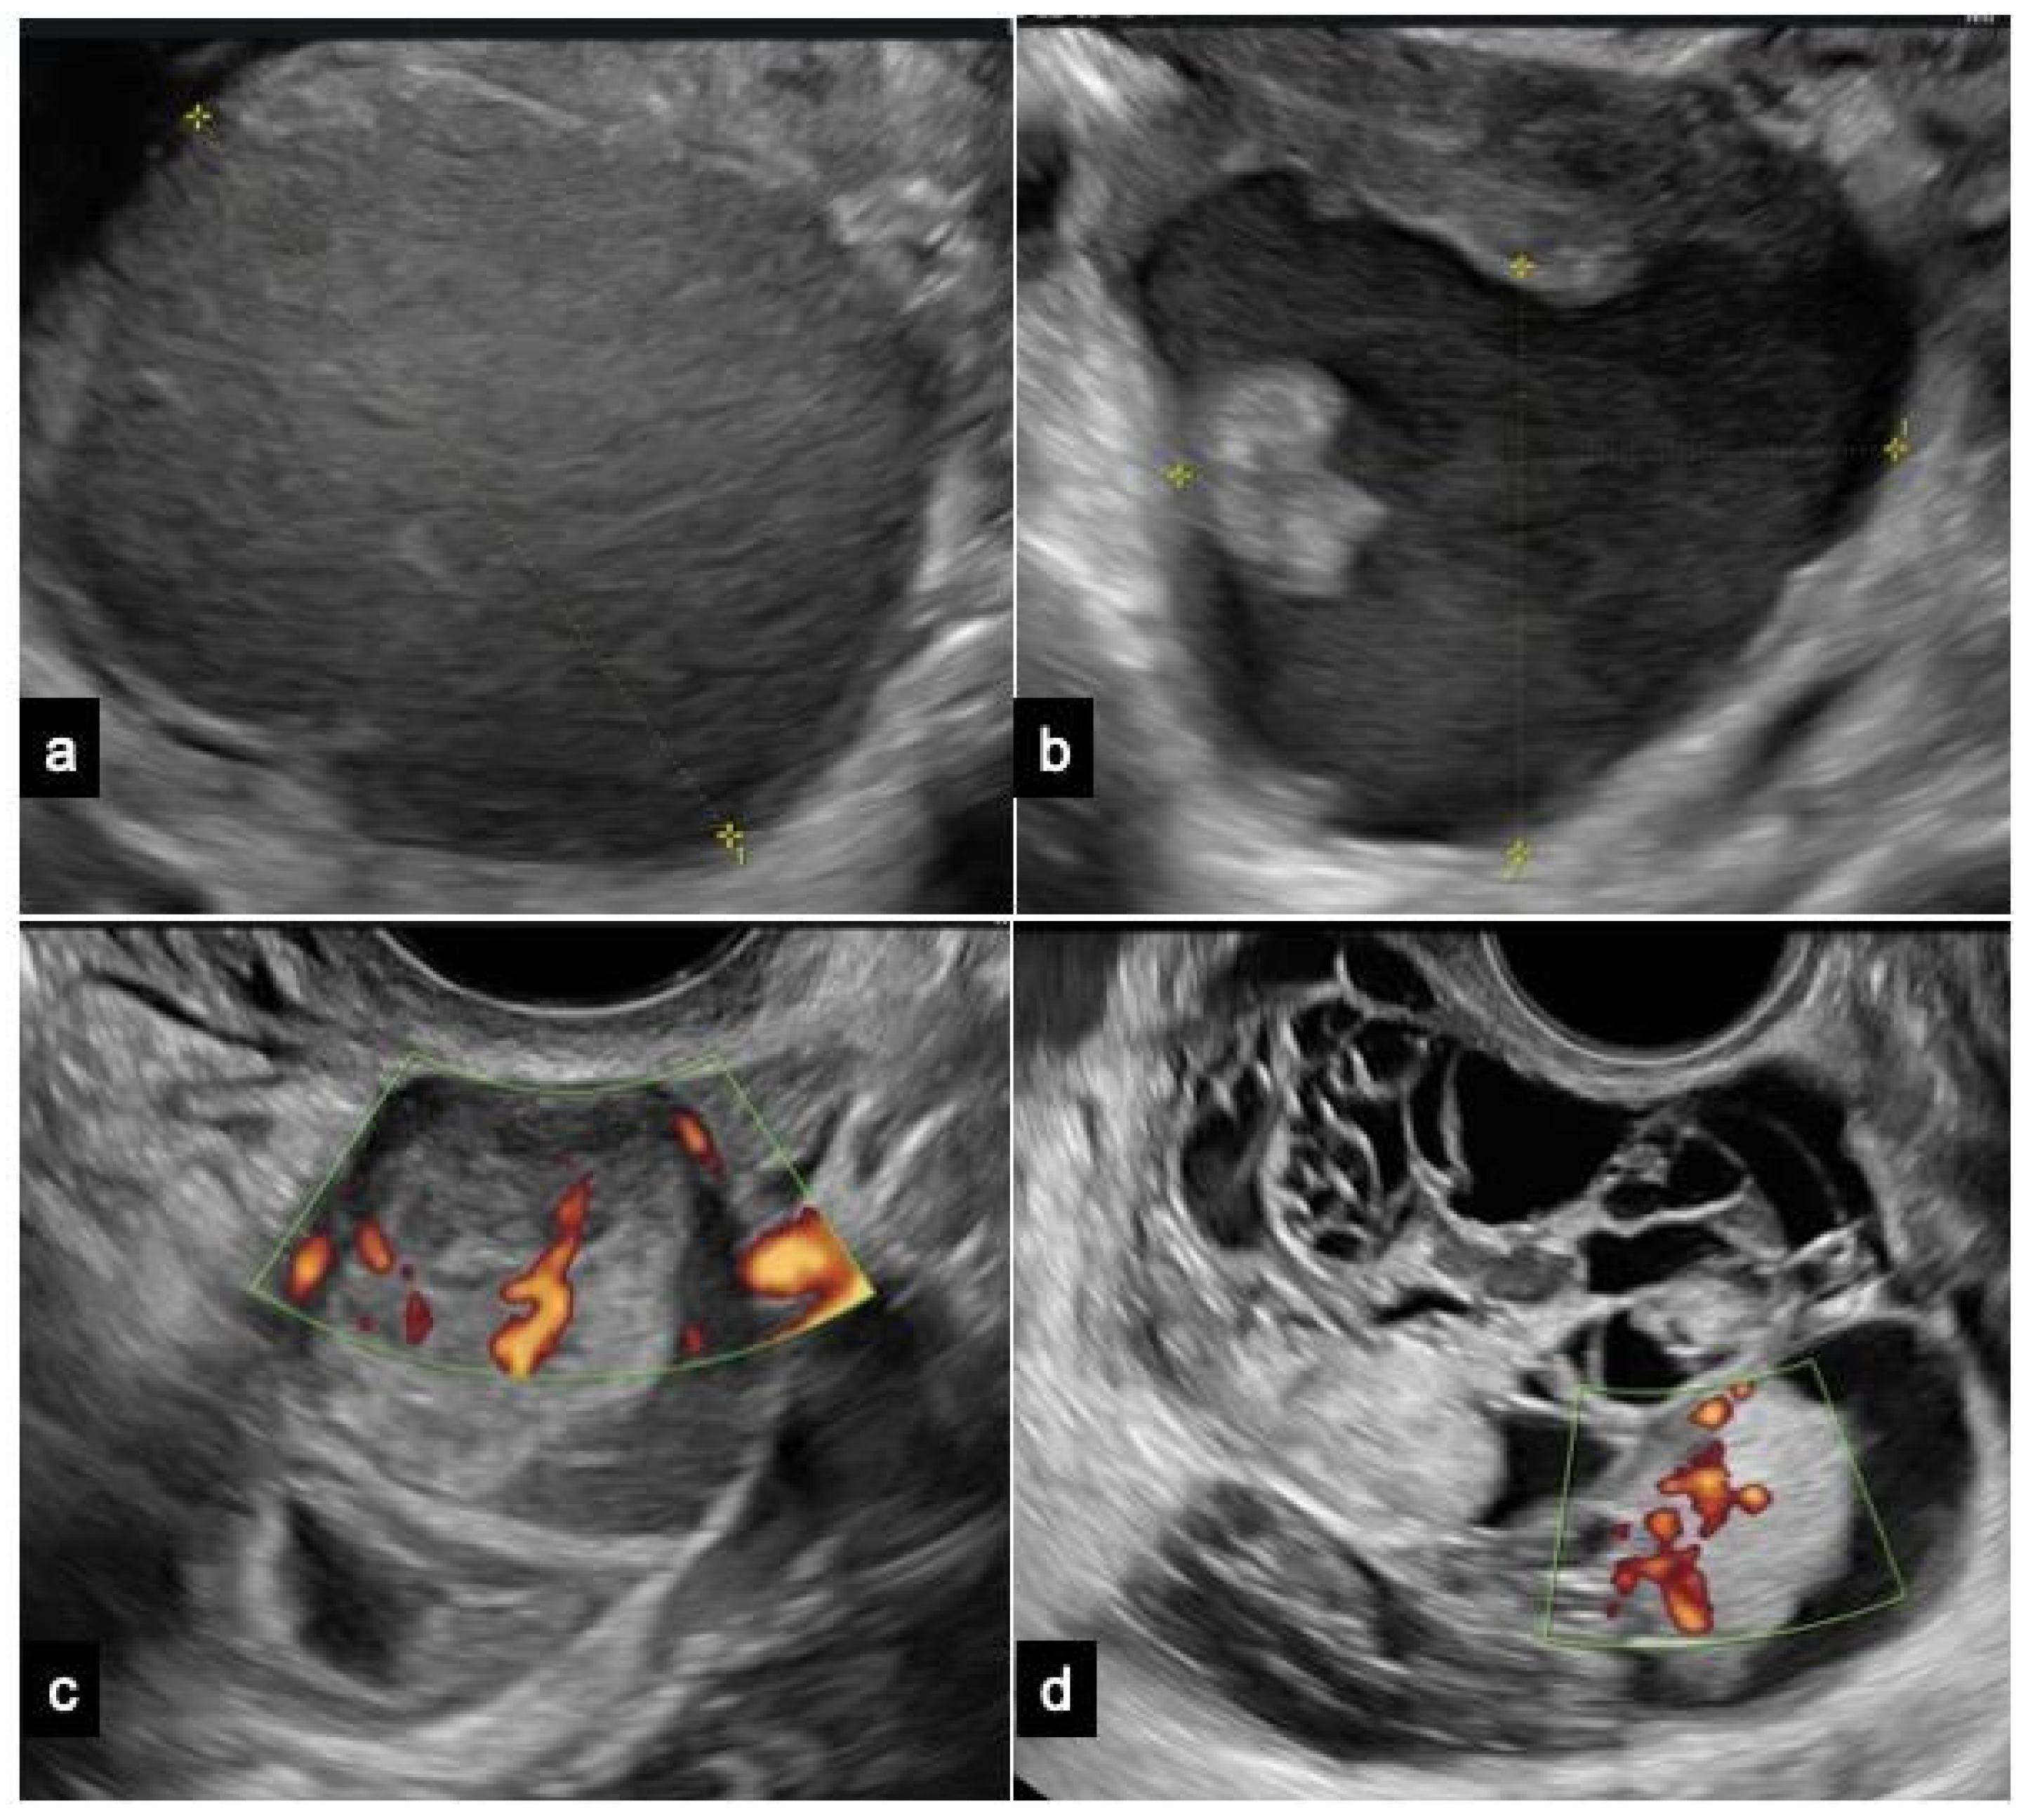

Endometrioma is predominantly a unilocular cyst displaying a uniform “ground-glass” echogenicity without observable solid or vascularized papillary components, facilitating its diagnosing in non-experienced hands (Figure 2).

Figure 2.

Ultrasound images of (a) a typical endometrioma, (b) an atypical endometrioma, (c) a clear cell carcinoma, and (d) an endometrioid carcinoma. The ultrasonographic diagnosis was confirmed by pathological examination, and patients provided informed consent for the use of their images.

However, endometrioma can be defined as atypical when at least one of the following sonographic characteristics is observed: cyst diameters of 10 ± 1 cm, multi-cystic formations, the presence of any solid component or papillary structure—defined by IOTA as a protrusion of solid tissue into a cyst cavity with a minimum height of 3 mm—and the detection of blood flow at any level [56,57]. The IOTA risk score considers unilocular cysts with small solid components (less than 7 mm of maximum diameters), acoustic shadows, uniform multilocular tumors with maximum diameters less than 10 cm, and the absence of blood flow as benign features. Malignant features encompass irregular solid tumors, ascites, four or more papillary structures, irregular multilocular solid tumors with a maximum diameter ≥10 cm, and strong blood flow. Typically, obtaining a histological evaluation post intervention for atypical endometriomas deemed at neoplastic risk is recommended. However, additional considerations, including patient’s age or fertility desires, are essential for determining the most appropriate management approach [56,58].

Ovarian CCC is typically diagnosed in its early stages, presenting as a sizable unilateral mass with solid components. Patients with CCC arising from endometriosis tend to be younger compared to those with non-endometriosis-associated clear cell carcinoma. Moreover, CCC originating from endometriosis may frequently display a ground-glass echogenicity in the cyst fluid [59].

EnOCs typically present as larger, unilateral, multilocular-solid, or solid tumors. The ultrasound features of EnOC originating from endometriosis exhibit distinctions from those not associated with endometriosis [52].

Borderline tumors and carcinomas originating from endometriomas typically show a vascularized solid component. An age of 45 years or older and endometrioma size of 8 cm or more are significant factors that independently predict the development of ovarian cancer in women with endometriomas [10,22,31].